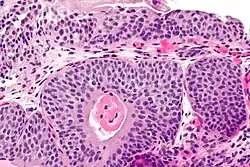

Cystitis cystica

| Micrograph showing cystitis cystica. | |